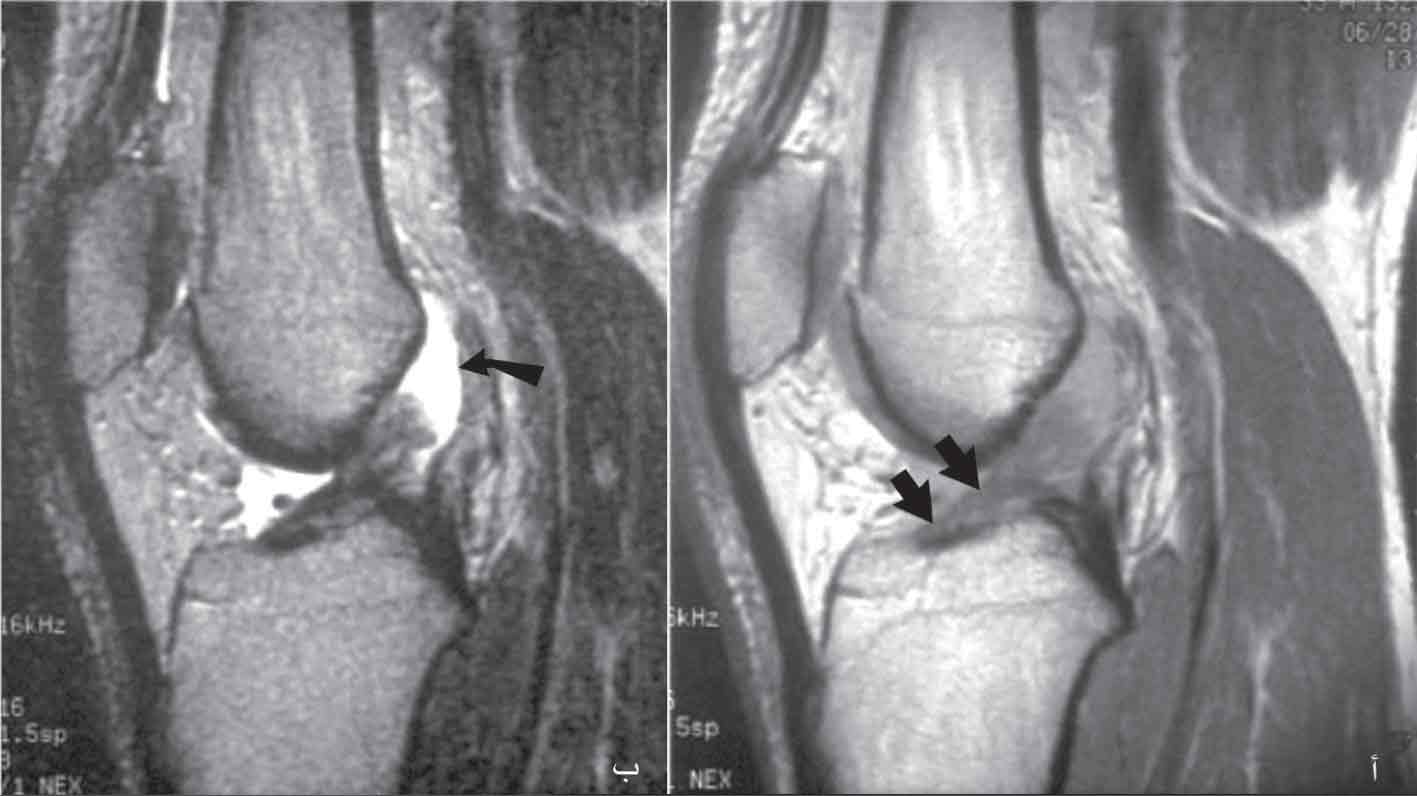

الفحص بالرنين المغنطيسي: هو الفحص الأكثر دقة لتشخيص إصابات الركبة الرباطية، فهو يميز الإصابات التامة من الجزئية، كما يظهر الكدمات العظمية في الجهة المقابلة للإصابة الرباطية، فله لذلك شأن في تحديد آلية الرض المسببة للأذية (الشكل26، 27, 28)

الشكل (27) تظهر صورة الرنين المغنطيسي أ- توذم الرباط المتصالب الأمامي، ب- توضع السائل مكان تمزق الرباط عن ارتكازه

الشكل (35) تصوير بالرنين المغنطيسي في سياق خلع ركبة: أ- غياب الرباطين المتصالبين الأمامي والخلفي دليل على تمزقهما، ب- انقطاع الرباط الجانبي الإنسي (رأس السهم) مع انقطاع الأربطة المتصالبة (السهم المتعرج)، ج- السبيل الحرقفي الظنبوبي الطبيعي بقسميه السطحي

الرنين المغنطيسي في سياق إصابة رباطية واسعة (بعد رد خلع مفصل الركبة أو الرد التلقائي).